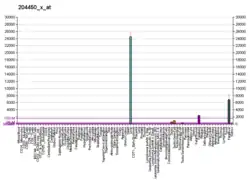

Interactive pathway map

Click on genes, proteins and metabolites below to link to respective articles.[§ 1]

- ↑ The interactive pathway map can be edited at WikiPathways: "Statin_Pathway_WP430".